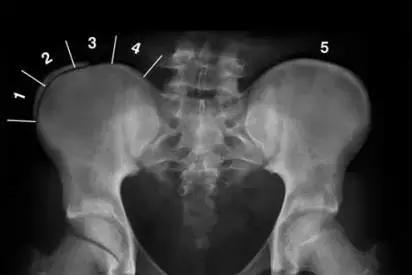

Risser征-发育指数

骨盆的Risser分级可以评估骨骼成熟度,评估出脊柱的生长发育潜能。骨骼成熟程度从0到5级,表示髂骨转换过程的钙化程度。处于0和1级的患者处于快速增长阶段,4和5级的患者已经停止生长。

Risser征-0到5级